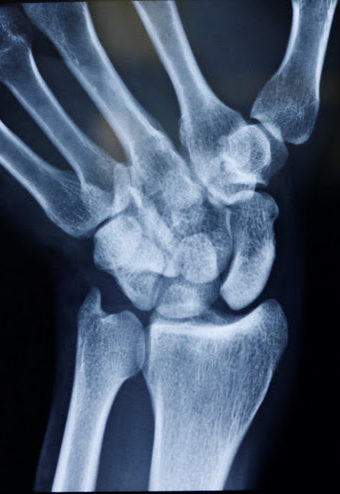

Skafolunat ekleminin ayrıldığını gösteren bileğin stresli görünümü